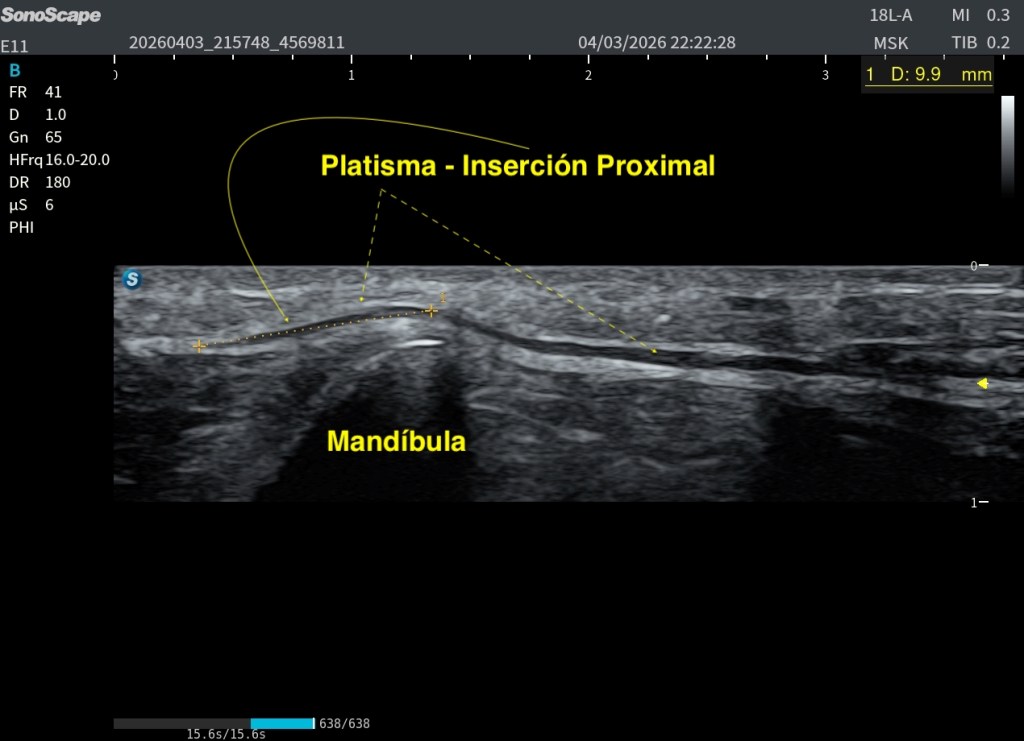

En su porción craneal, se inserta principalmente en la mandíbula y, sobre todo, en la piel y musculatura facial, conectando con el Orbicular de la boca y el Depresor del ángulo de la boca. La inserción ósea es secundaria, predominando su función en la mímica facial. Además algunos estudios dicen que depende tambien de la edad del porteador, acortándose la inserción proximal con la edad del porteador.

El Platisma se presta especialmente bien a la evaluación mediante técnicas de campo extendido. Utilizando el modo panoramic view, es posible realizar un recorrido continuo del músculo y obtener una visión global de su extensión, algo muy útil dada su morfología plana y superficial.

La exploración puede realizarse en eje axial (corte corto respecto al cuello), desplazando la sonda de forma progresiva a lo largo del trayecto del músculo. Esto permite visualizar su continuidad lateral y entender mejor su disposición en el plano subcutáneo. También puede intentarse un estudio bilateral, tratando de integrar ambos lados en una única imagen panorámica.

A pesar de estas limitaciones, el platisma, por ser un músculo muy extenso, plano y superficial, se adapta bien a este tipo de exploración, y la panoramic view se convierte en una herramienta especialmente útil para comprender su anatomía global y su continuidad. Podemos medirlo tambien.

Para cerrar el post con una visión rigurosa y útil en práctica clínica, despues de haber revisado mucho, es importante entender que el Platisma no dispone de valores estándar universales de grosor o tamaño como otros músculos. La literatura científica actual describe más su variabilidad anatómica y funcional que una medida normal fija. Por ejemplo, en un estudio reciente sobre su inserción craneal, se observó que la altura máxima de inserción se sitúa en 2,9 ± 1,0 cm por encima del ángulo mandibular, disminuyendo con la edad aproximadamente 0,54 mm por año, lo que confirma que su morfología cambia con el envejecimiento (Hwang et al., 2017; estudios posteriores de validación ecográfica), esto es superinteresante.